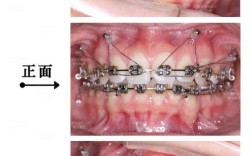

牙齿矫正的本质是利用外力(如托槽、弓丝、橡皮筋等)引导牙齿在牙槽骨中缓慢移动,从而排列整齐、调整咬合,而牙齿移动时,需要对抗“支抗”——即抵抗牙齿移动的反作用力,想要将前牙(门牙)向后移动改善“龅牙”,就需要后牙(磨牙)作为“支抗”保持不动;但如果后牙本身的支抗能力不足,就可能随前牙一同移动,导致矫正效果打折扣。

传统矫正中,支抗主要依赖牙齿之间的相互支撑(如“颌内支抗”——用一组牙移动另一组牙,“颌间支抗”——上下颌牙齿相互牵引),但这种方式存在局限性:一是支抗强度有限,尤其当需要大幅移动牙齿时,易发生支抗丢失;二是无法精准控制牙齿移动方向,可能出现非预期的倾斜、旋转等问题,种植钉就成为了“支抗强化”的关键工具。

种植钉的优势在于它能直接植入牙槽骨,与骨骼形成稳定的骨结合(虽不如种植牙牢固,但足以提供足够支抗),且不依赖其他牙齿,因此被称为“绝对支抗”,其具体作用可归纳为以下几点:

牙齿移动的理想状态是“整体平动”(如整颗牙平行移动),而非“倾斜移动”,压低过长的牙齿(如因牙龈萎缩导致的“露龈笑”磨牙),若仅用传统弓丝,易导致牙齿冠根反向移动(牙冠压低、牙根升高);而通过在牙槽骨中植入种植钉,再借助橡皮筋或弹簧施加力量,可实现牙齿的“垂直压低”,避免牙根损伤。